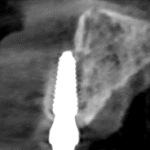

CT Xray after 22 months loading: stable bone around implant, no inflamation